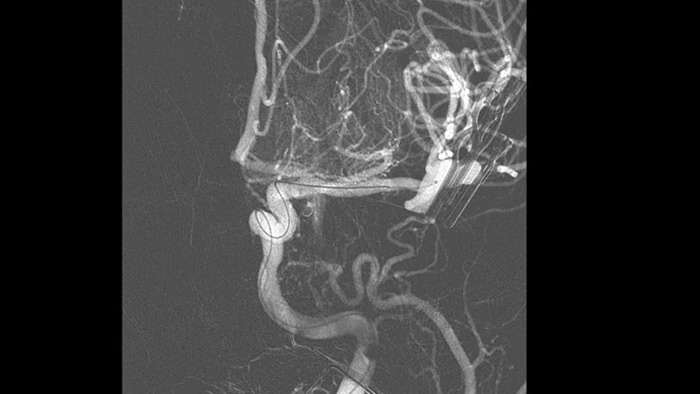

Anatomical references support precise 3D navigation

SmartCT Roadmap precise 3D navigation

SmartCT Roadmap provides anatomical references to support navigation of guidewire, catheter and device to the clot.

Enhance visualization of vasculature

Roadmap Pro

Make informed decisions about whether the clot can be reached and which route to use. Roadmap Pro, an advanced double contrast roadmap, helps enhance visualization of overlapping vessels, while balancing radiation exposure.